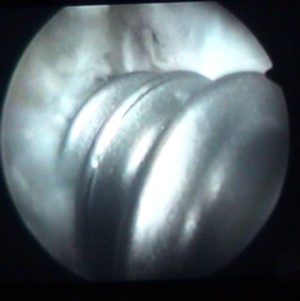

enlèvement d'un ménisque |